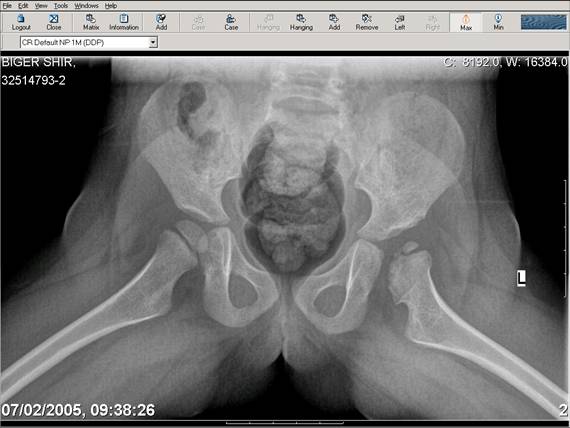

Navernoe Dega

Chto by ne byt goloslovnym posilau vam svoi sluchai gde sdelal vse chto napisal vyshe

Mark Eidelman